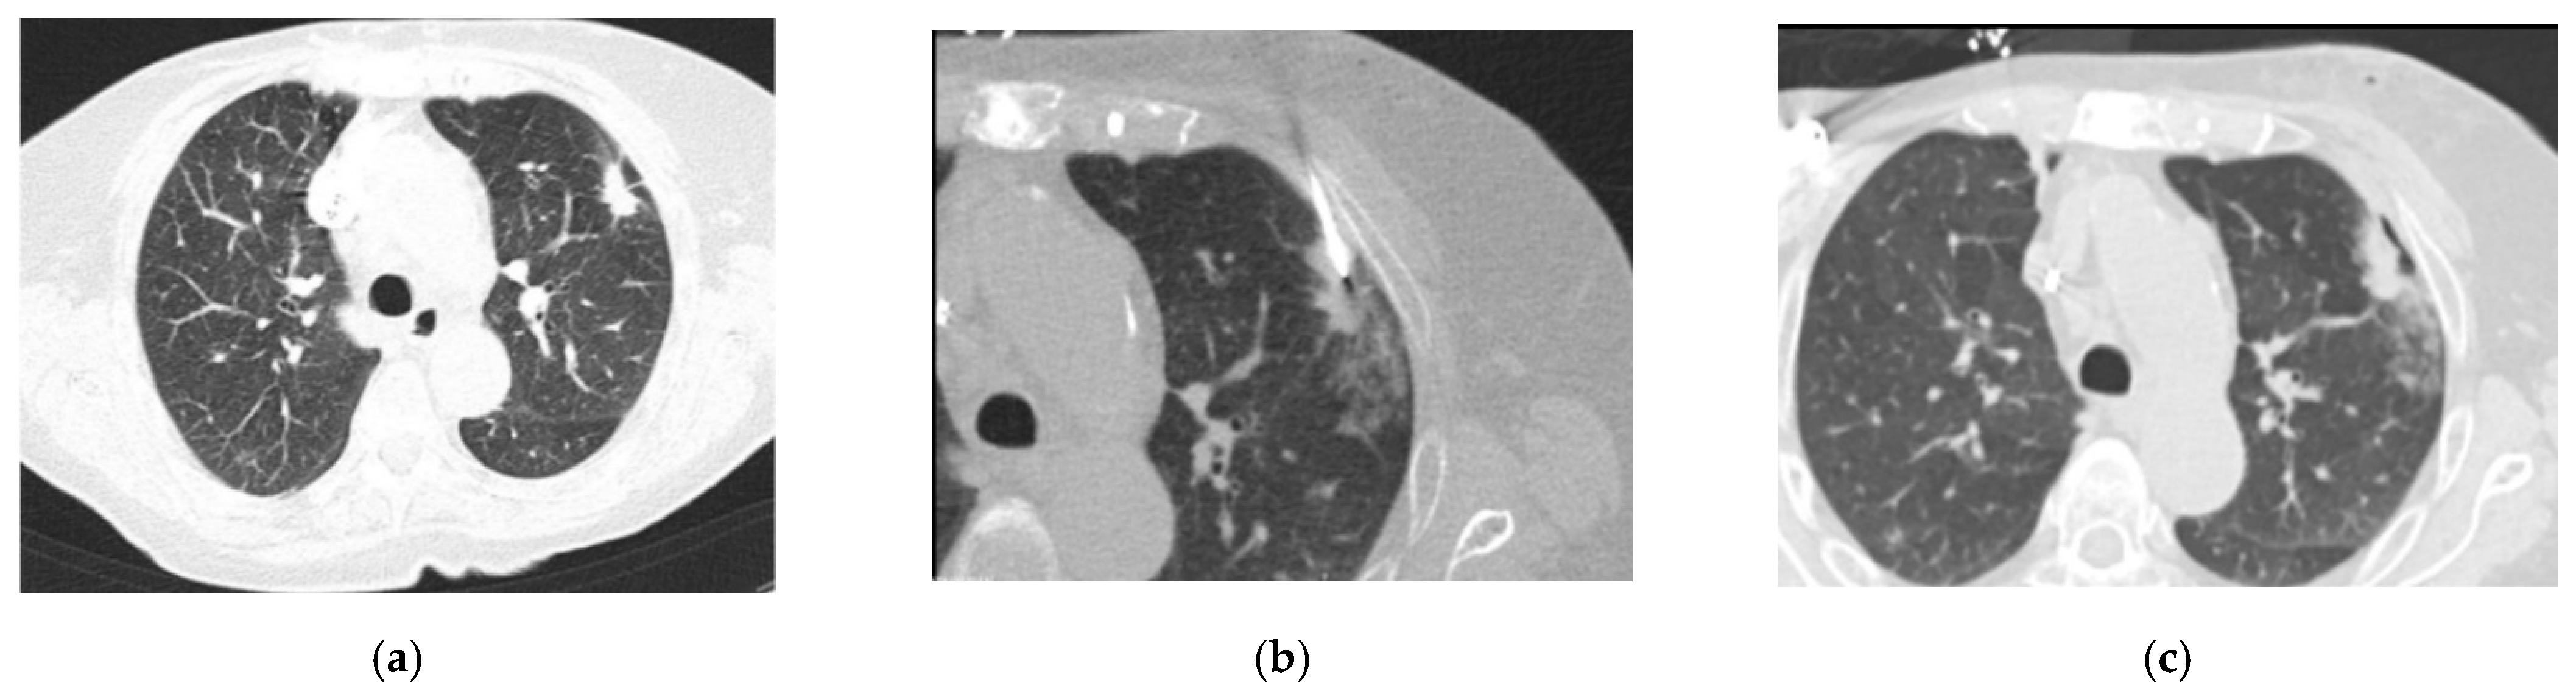

Figure 2a–c shows a pulmonary mass that was punctured during our study. Due to the adjacent rib, the needle’s angle to the pleura had to be rather shallow, as can be seen in Figure 2. The post-interventional control scan (Figure 2c) shows a small, clinically stable pneumothorax in the access pathway.

Axial CT images of the lungs conducted with the use of 90 mAs at 120 kV, and a 3 mm slice thickness with a 2 mm increment: (a) a pulmonary mass seen on the left, immediately before the biopsy; (b) the needle entering the pleura at an angle away from the perpendicular; and (c) a stable pneumothorax observed in the post-biopsy CT scan.